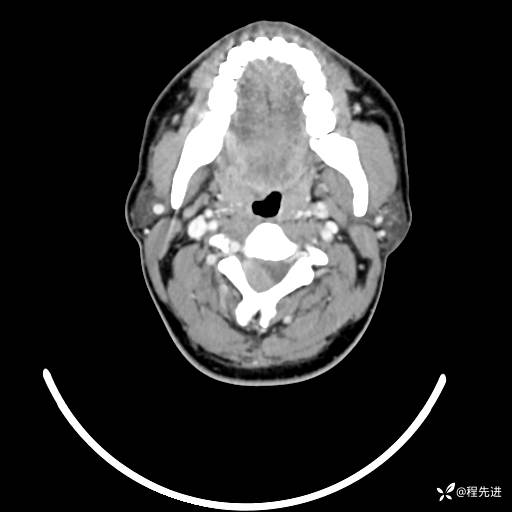

CT平扫+增强: